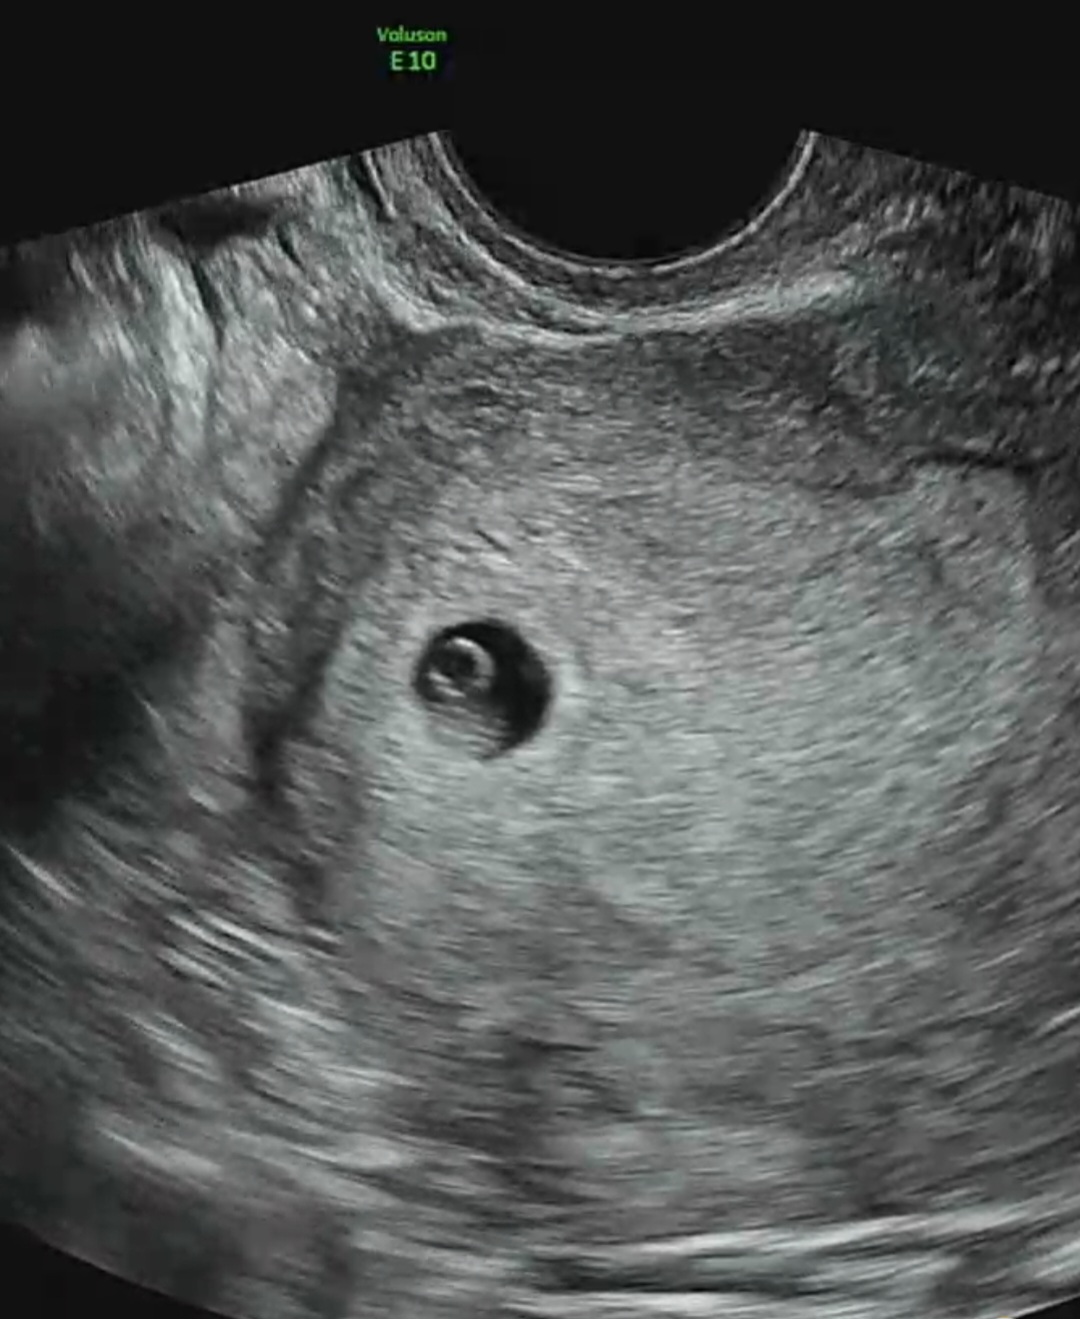

5주 3일차에 병원 방문해 초음파로 아기집과 난황 확인까지 했어요. 초산이지만 8월에 고사난자 판정으로 소파술 1회 받았습니다. 병원에서 아기집이 너무 작다고 하는데 이시기에 아기집 1cm 면 작은건가요? 2cm 정도는 되어야 될것 같다고 하시네요ㅠㅠ 그래도 베동글 보면 비슷한 사이즈 많이있던데 자궁경부가 짧다는말도 하셔서 이래저래 걱정이 크네요.

오잉 저두 5주1일차에 병원가서 아기집 보고왔는데 6mm였어요!! 그런데 의사선생님이 아주 잘 자리잡고 다 정상이고 좋다고 하셨어요☺️ 사진보니 저랑 위치나 모양 다 비슷하신데요?!! 너무 걱정마셔요‼️

오잉 5주차 초반때 난 6mm였구 지금은 심장소리까지 들리는 7주차 들어섬! 난 5주차때 딱히 그런 소리 못 들었는디….